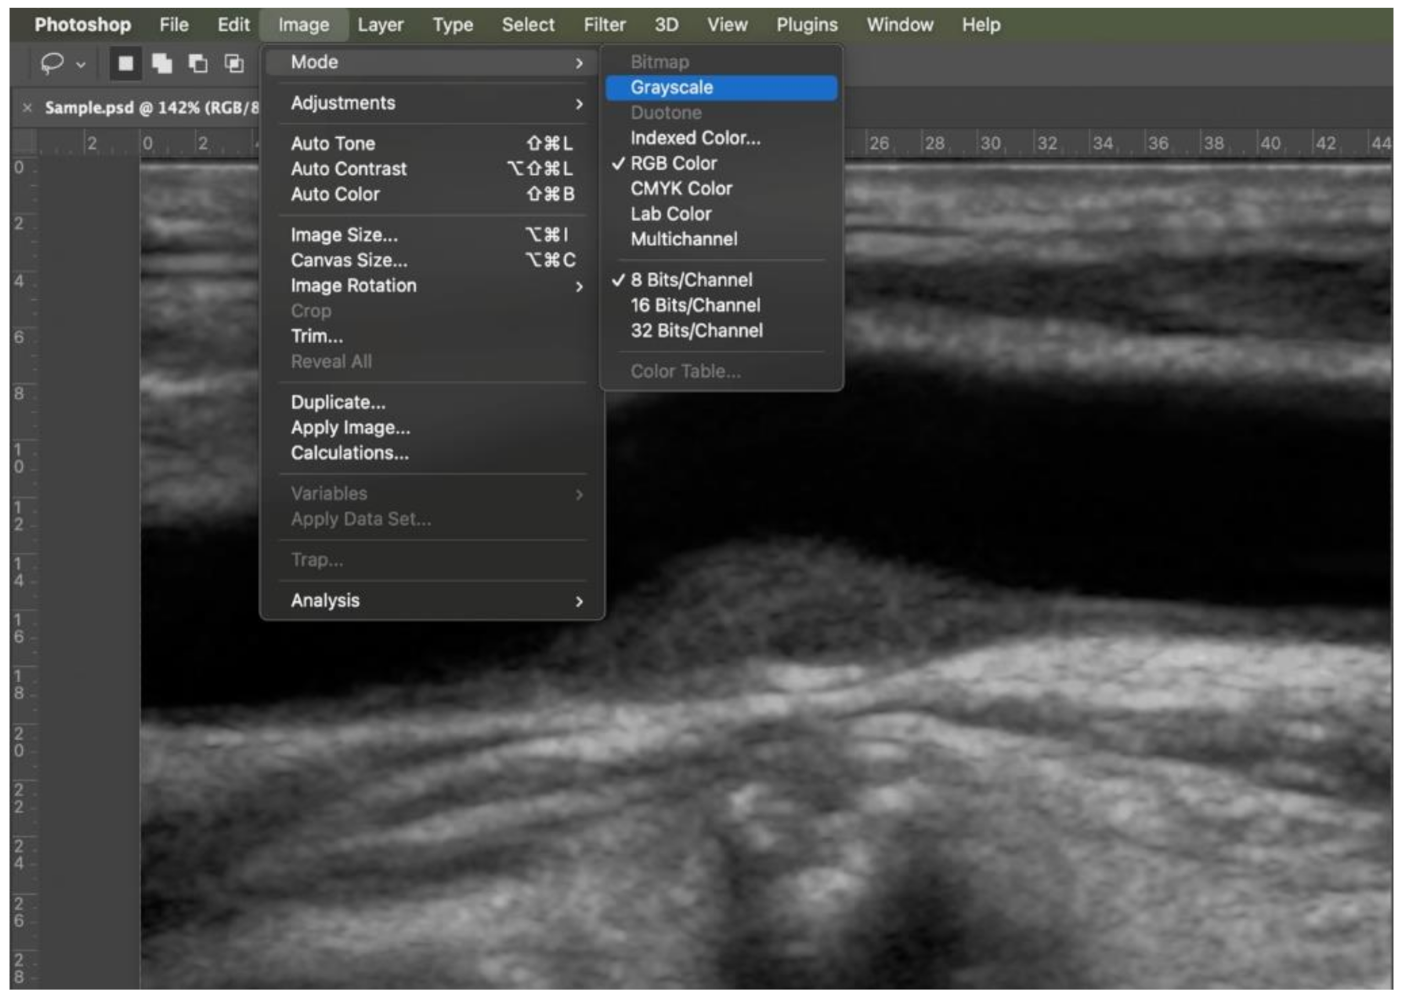

It was standardized at 70 dB and 4.0 cm depth, with overall and time-gain compensation optimized for each patient, using an iU22 scanner (Philips North America Corporation, Andover, MA, USA) and an L12–5 (7.5 MHz) broadband linear transducer. A correct setup is shown in Figure 1 to reduce B-mode gain and to eliminate background noise, the blood should be completely black.

Figure 1.

An example of correct doppler US set up with a gently curved line.

First step: color information was eliminated by transforming a red, green, blue (RGB), 8 bit image into a grey scale, 8 bit image (Figure 2).

Figure 2.

Step 1: transformation into a grey scale 8 bit image (Image > Mode).